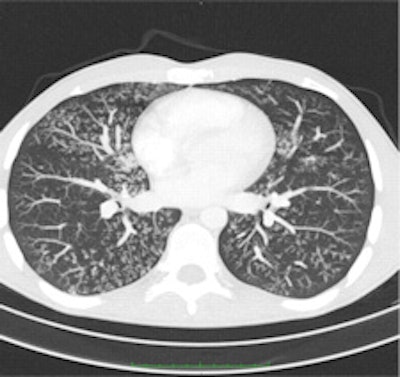

Maximum intensity projection (MIP, left) and minimum intensity projection (MinIP, right) images were calculated on demand by 24 (49%) and 20 (41%), respectively, of the survey's respondents. MIPs are particularly helpful in detecting small pulmonary nodules and determining the distribution of the nodules. MinIPs are used to ease the detection and quantification of subtle emphysema. All images provided by Dr. Helmut Prosch."The message we want to send is that state-of-the art CT protocols should include volume datasets with dose modulation switched on and the tube potential adjusted to the age and size of the patient," Prosch added. "While many radiologists use dose modulation tools, not all define the kVp depending on the patient."

Chest CT with activated automatic dose modulation. Automatic dose modulation reduces the radiation dose by adjusting the dose along the patient's length axis. Dose modulation allows a dose reduction of up to 30%.The risk of radiation-induced cancer is real but its extent is not yet fully understood, given that current thinking is based mainly on data extrapolated from Hiroshima and that it remains hard to discern radiation-induced cancer from that which is nonradiation induced, he explained. Because CT answers a lot of questions that simple chest x-ray can't, and because treatment depends on these CT results, the modality is being increasingly used, and radiation dose to the whole population is growing year by year.